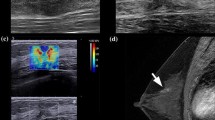

An example for calculating the fmass for a 59-year-old female patient with grade II invasive ductal carcinoma. a The mass size d was read as the greatest dimension shown in the clinical B-mode image, and it is 28 mm in this example. b The minimum shear wave speed was calculated as the average value of the minimum shear wave speed from the three ROIs shown in the SWE image and is 2.7 m/s. Therefore, the fmass for this measurement is 96 Hz. ROI, region of interest; SWE, shear wave elastography

For all three visits, non-responders showed higher averaged elasticity, elasticity ratio, and lower mass characteristic frequency. No significant difference was found in the change of elasticity, although there was a trend for the averaged change in stiffness in the responder group to be higher. A significant difference was found in the change of the mass characteristic frequency measured between the first and the third visits (fmass1–3, p < 0.001). Figures 3 and 4 show the typical SWS maps for a responder and a non-responder for the three SWE studies, respectively; Emean and fmass for different molecular subtypes measured during the three visits are shown in Figs. 5 and 6, respectively, indicating that stiffness decreased significantly for the responders, while remained high for the non-responders; the fmass remained low for non-responders and increased significantly for responders.

Shear wave speed map for a 48-year-old female with HER2+ tumor (grade III invasive ductal carcinoma) measured a before NACT, b during the mid-course of NACT, and c after NACT but before surgery. The mean elasticity, maximum elasticity, and mass characteristic frequency are shown in d. This is a responder with RCB score of 0. NACT, neoadjuvant chemotherapy; RCB, residual cancer burden

Shear wave speed map for a 59-year-old female with Luminal A tumor (grade II invasive ductal carcinoma) measured a before NACT, b during the mid-course of NACT, and c after NACT but before surgery. The mean elasticity, maximum elasticity, and mass characteristic frequency are shown in d. This is a non-responder with an RCB score of 1.6. NACT, neoadjuvant chemotherapy; RCB, residual cancer burden